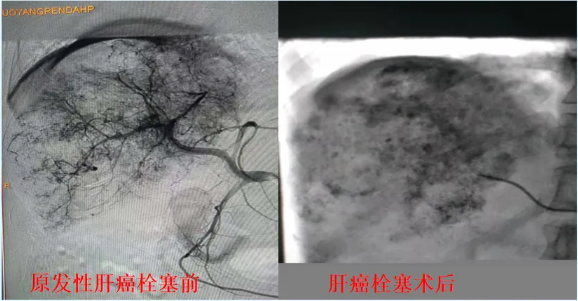

通过肝动脉化疗栓塞术等,精准打击肿瘤,延长患者生存期。